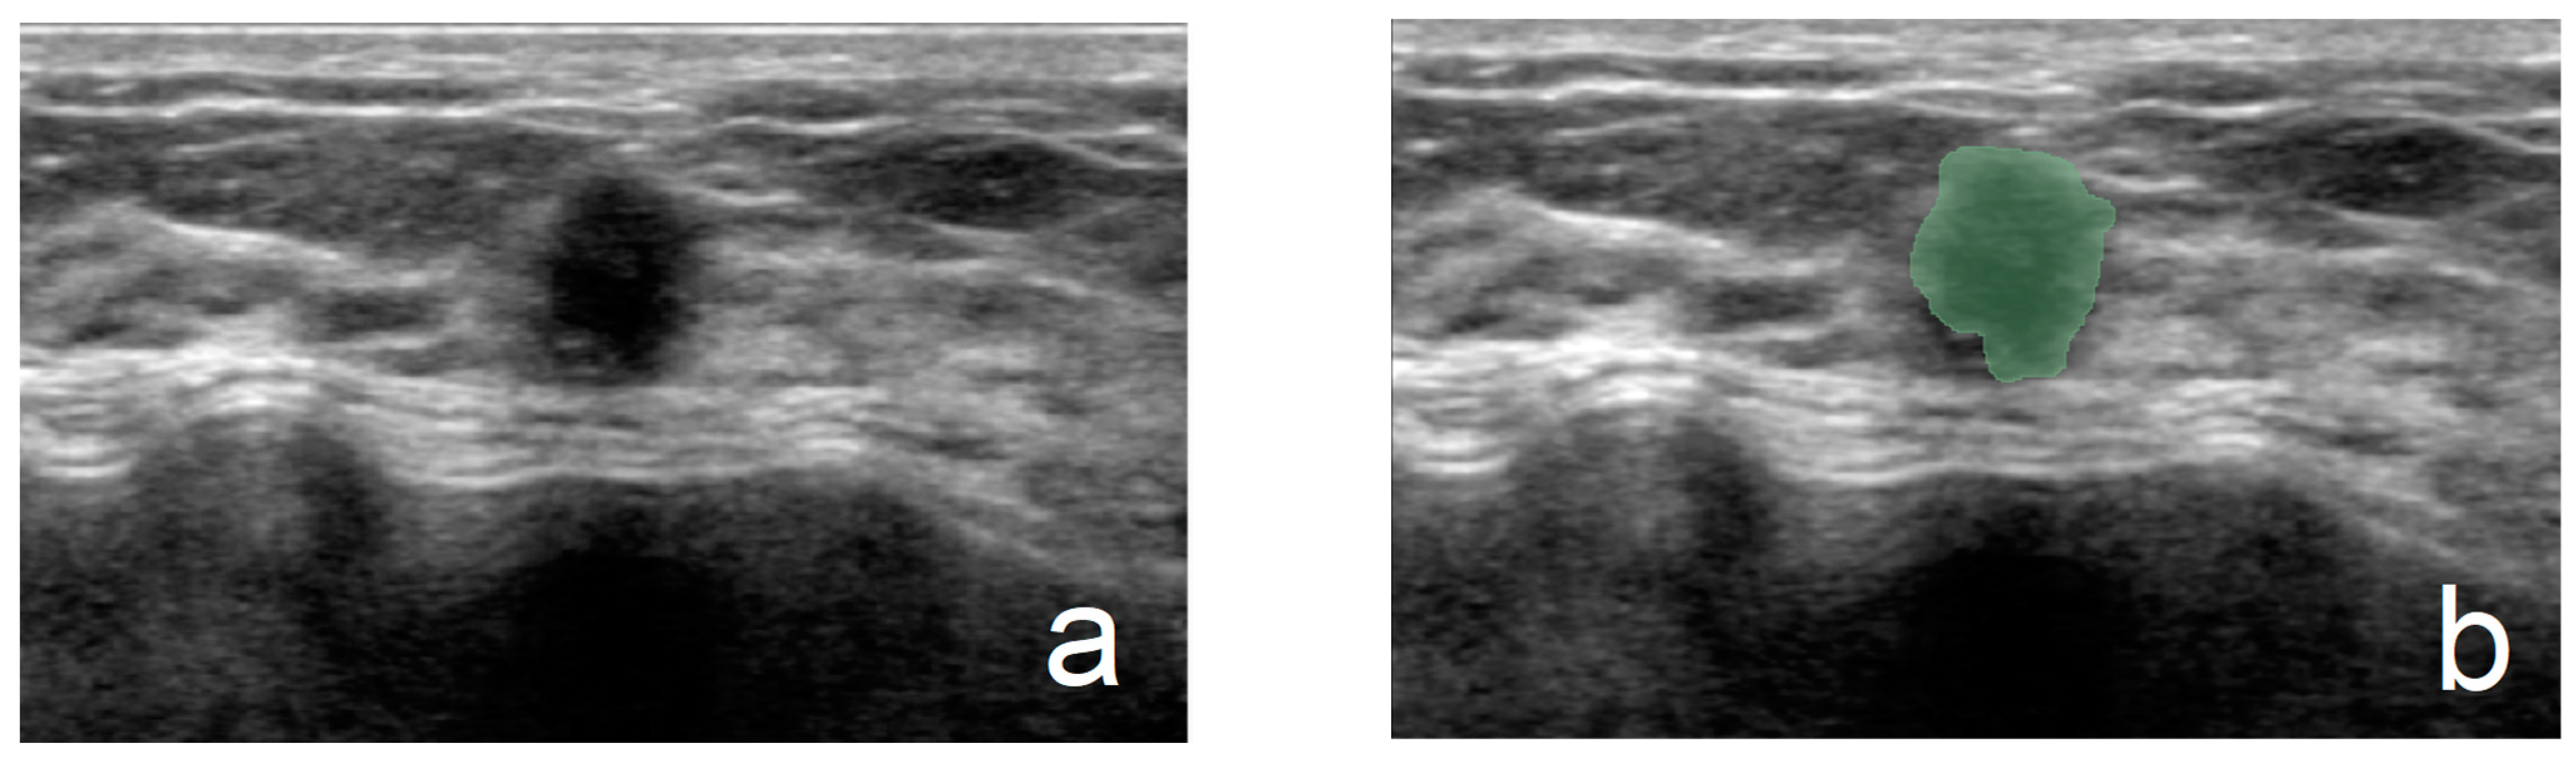

2.4. Acquisition of Ultrasound Pictures, Preprocessing, and ROI Delineation